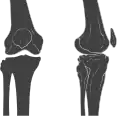

In humans and other primates, the knee joins the thigh with the leg and consists of two joints: one between the femur and tibia (tibiofemoral joint), and one between the femur and patella (patellofemoral joint).[1] It is the largest joint in the human body.[2] The knee is a modified hinge joint, which permits flexion and extension as well as slight internal and external rotation. The knee is vulnerable to injury and to the development of osteoarthritis.

Structure

The knee is a modified hinge joint, a type of synovial joint, which is composed of three functional compartments: the patellofemoral articulation, consisting of the patella, or "kneecap", and the patellar groove on the front of the femur through which it slides; and the medial and lateral tibiofemoral articulations linking the femur, or thigh bone, with the tibia, the main bone of the lower leg.[6] The joint is bathed in synovial fluid which is contained inside the synovial membrane called the joint capsule. The posterolateral corner of the knee is an area that has recently been the subject of renewed scrutiny and research.[7]